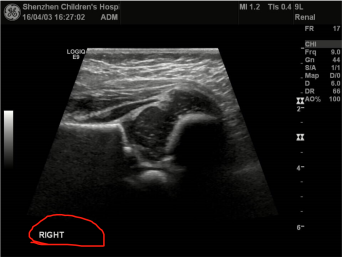

人体髋关节。对每一个人的髋关节有左右两个图像。

目前我们标记的数据,都是从视频中找出左侧骨头最水平的一张,抽出来标记。